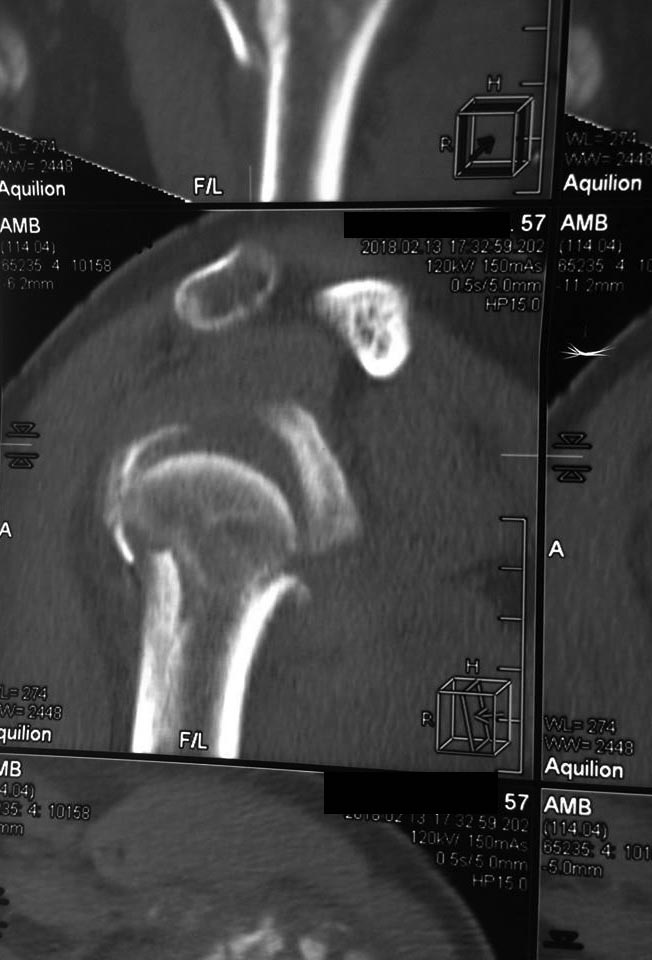

На снимках плечо вывихнуто. По ркт- открытая репозиция и пластина с угловой стабильностью LCP . Все просто.

Склоняюсь к пластине, по крайней мере на протез потом уйти можно

Делать синтез. Пластиной. Быть готовым к костной пластике после оппозиции головки. Главное вернуть на место бугорки с манжетой. Можно и протез но не реверс а анатомический.

В возрасте до 60 лет - ORIF. Пластика не нужна. Самое важное прошить и фиксировать сухожилия манжеты к имплантату. Я бы предпочел Multiloc.